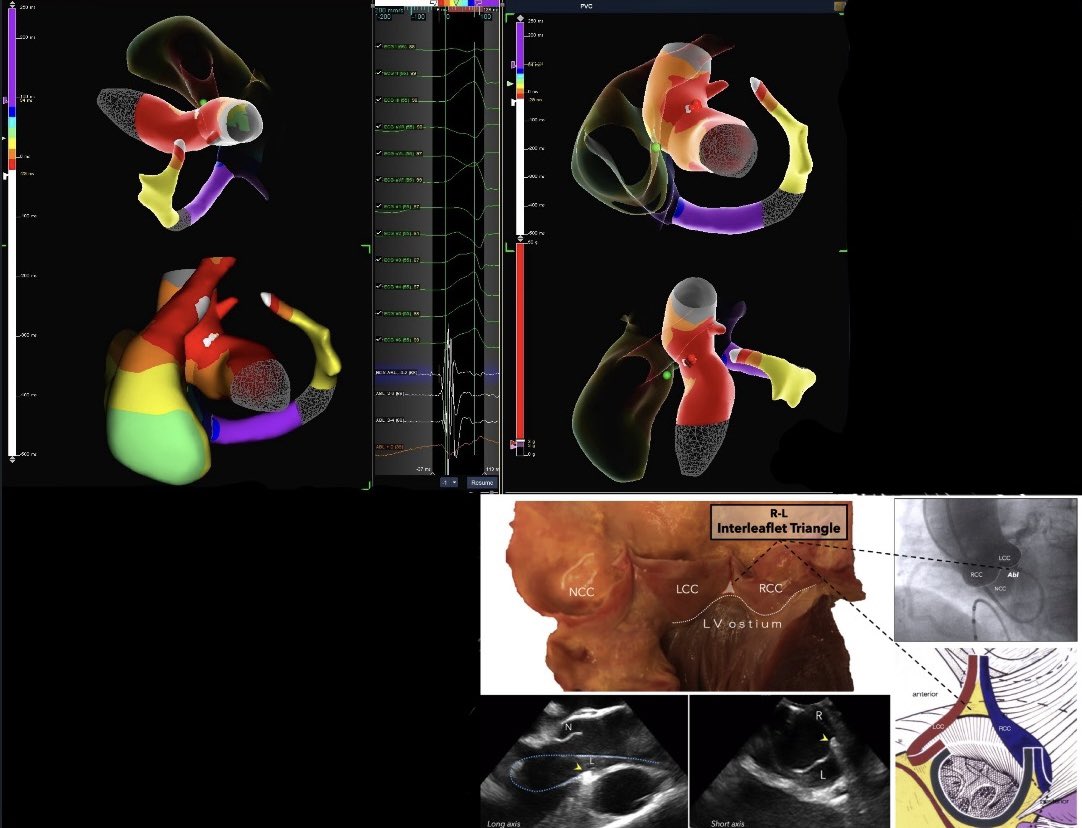

Atrial late activation mapping in a patient with recurrence after PVI + anterior mitral line. Latest activated zone with fragmented signals during sinus rhythm predicts critical isthmus of roof- dependent macro-reentry & successful termination site. #EPeeps